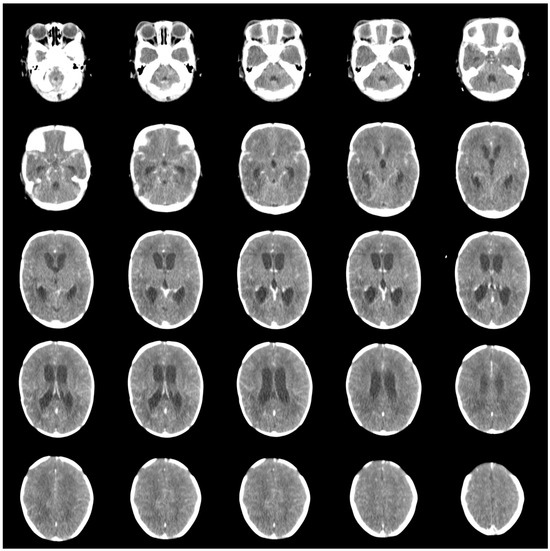

2.1. Patient 1

2.2. Patient 2

2.3. Patient 3

2.4. Patient 4